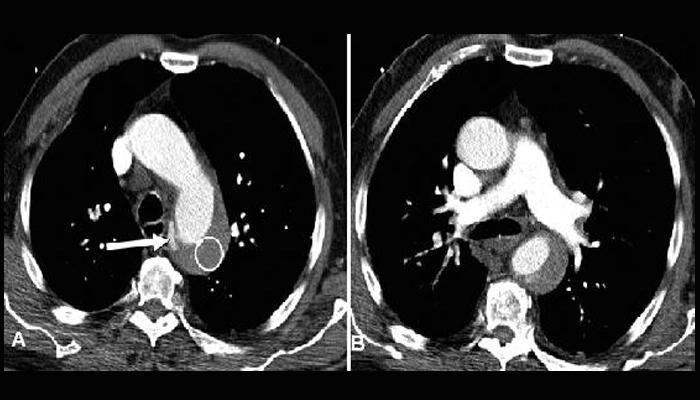

Chụp cắt lớp vi tính (CT-angiography): tiêu chuẩn vàng, cho hình ảnh rõ vị trí và mức độ bóc tách.

Ảnh CT có tiêm thuốc cản quang cho thấy cục máu đông trong lòng giả ở bệnh nhân bóc tách động mạch chủ.